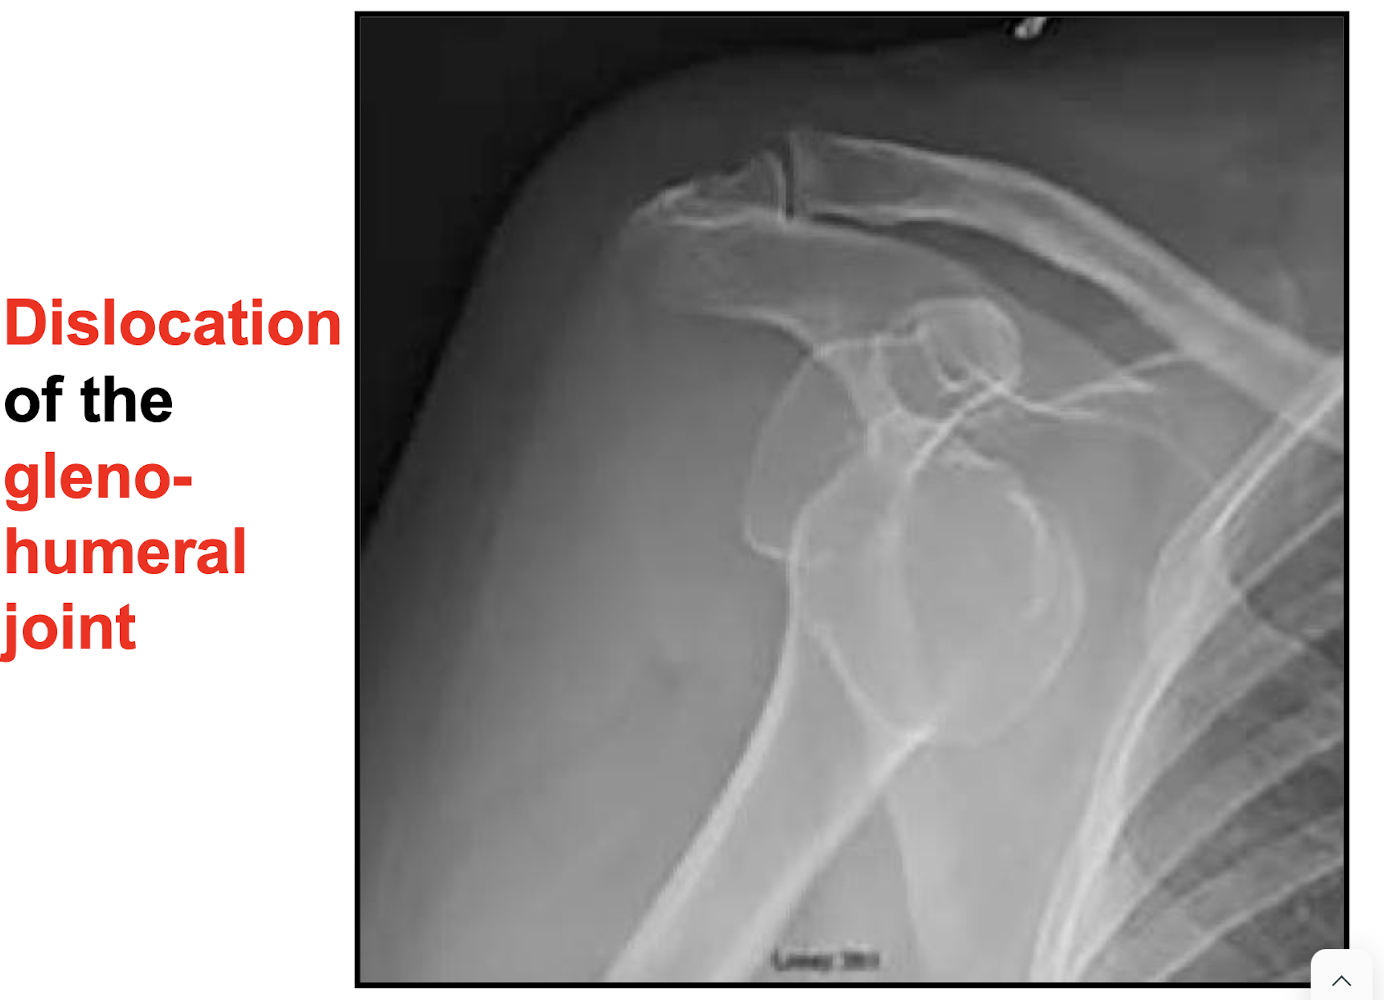

What is the consequence of the mobility of the glenohumeral joint?

Mobility brings instability such as subluxation and dislocation

Where is the axillary nerve uniquely vulnerable to injury?

At the surgical neck of the humerus (tearing) and during glenohumeral dislocation (stretching/tearing).